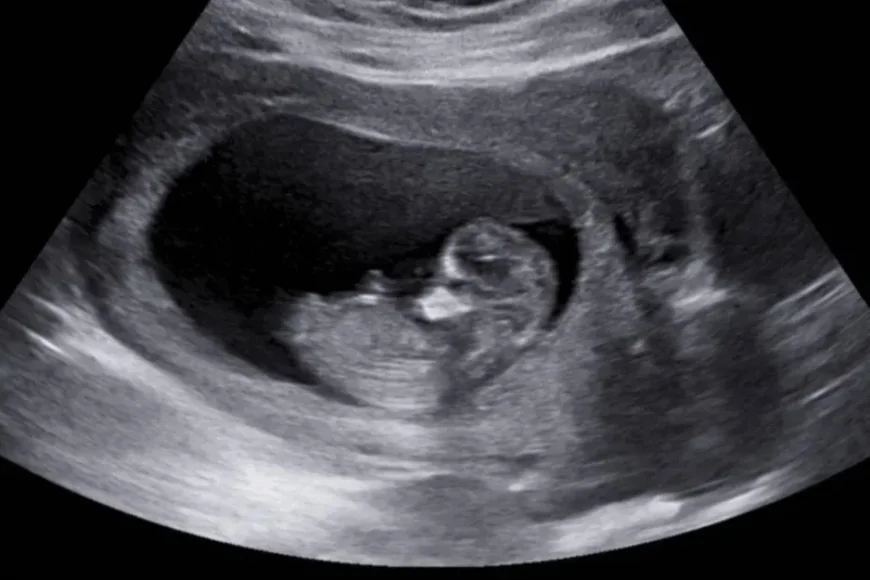

ABD’deki bilim insanları, tarih yazacak bir başarıya imza attı. Spinal Müsküler Atrofi (SMA) hastalığına sahip bir fetüs, anne karnında yapılan tedaviyle sağlıklı bir şekilde doğdu. Bu tedavi, SMA hastalığı için bir dönüm noktası olarak kabul ediliyor. Araştırma, The New England Journal of Medicine‘de yayımlandı.

Çalışmada, SMA belirtileri gösteren bir fetüs üzerinde tedavi uygulandı. Ebeveynler, daha önce SMA nedeniyle bir bebeklerini kaybettikleri için bu yeni tedaviye katılmayı kabul ettiler. ABD Gıda ve İlaç Dairesi (FDA), bu tedavi için tek seferliğine ilacın doğum öncesi kullanımına onay verdi. SMA tedavisinde etkili olan Risdiplam adlı ilaç, anneye altı hafta boyunca günlük dozda verildi. Doğumdan sonra ise ilaç, direkt olarak bebeğe oral yoldan verildi.